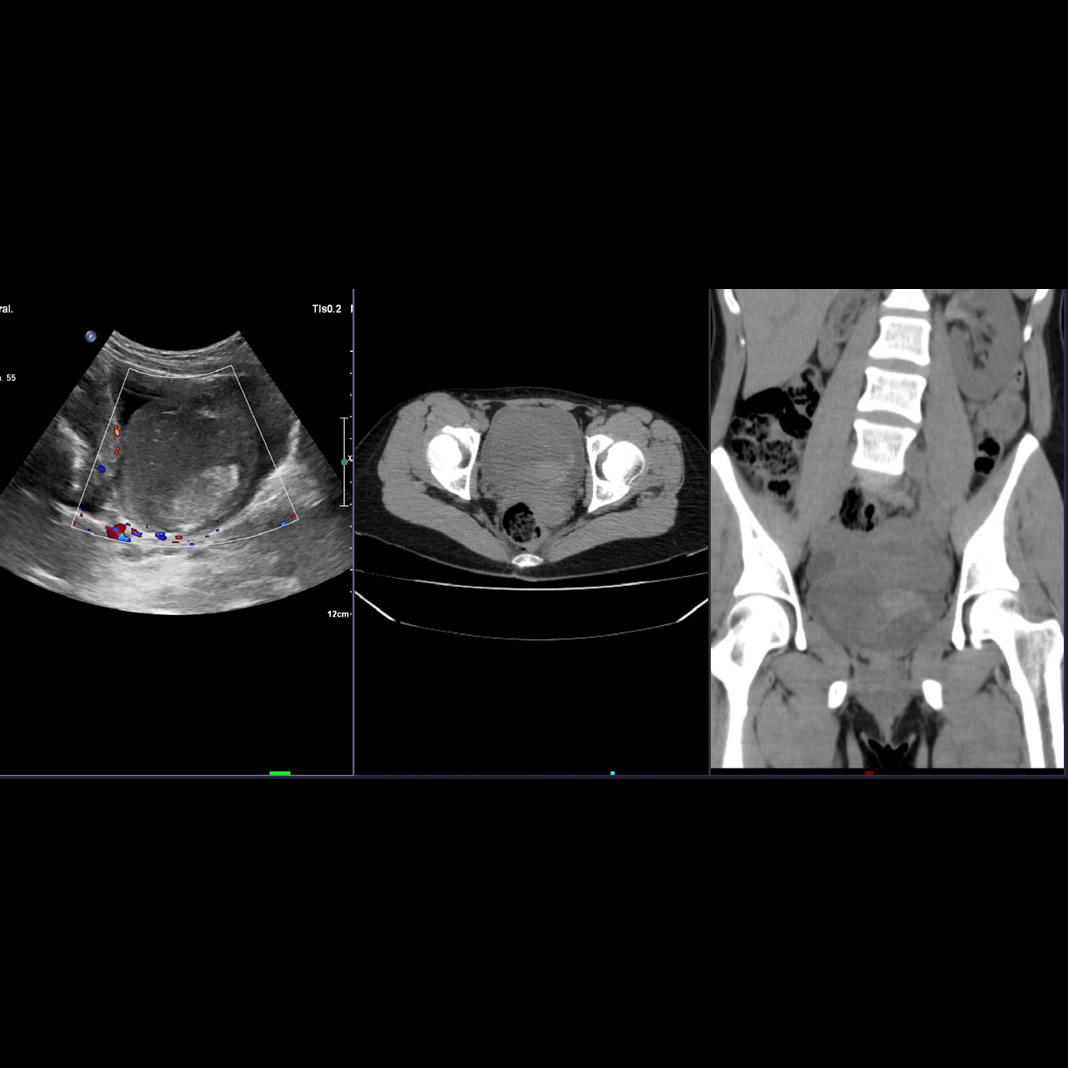

Paciente sexo femenino de 39 años con lumbalgia y hematuria